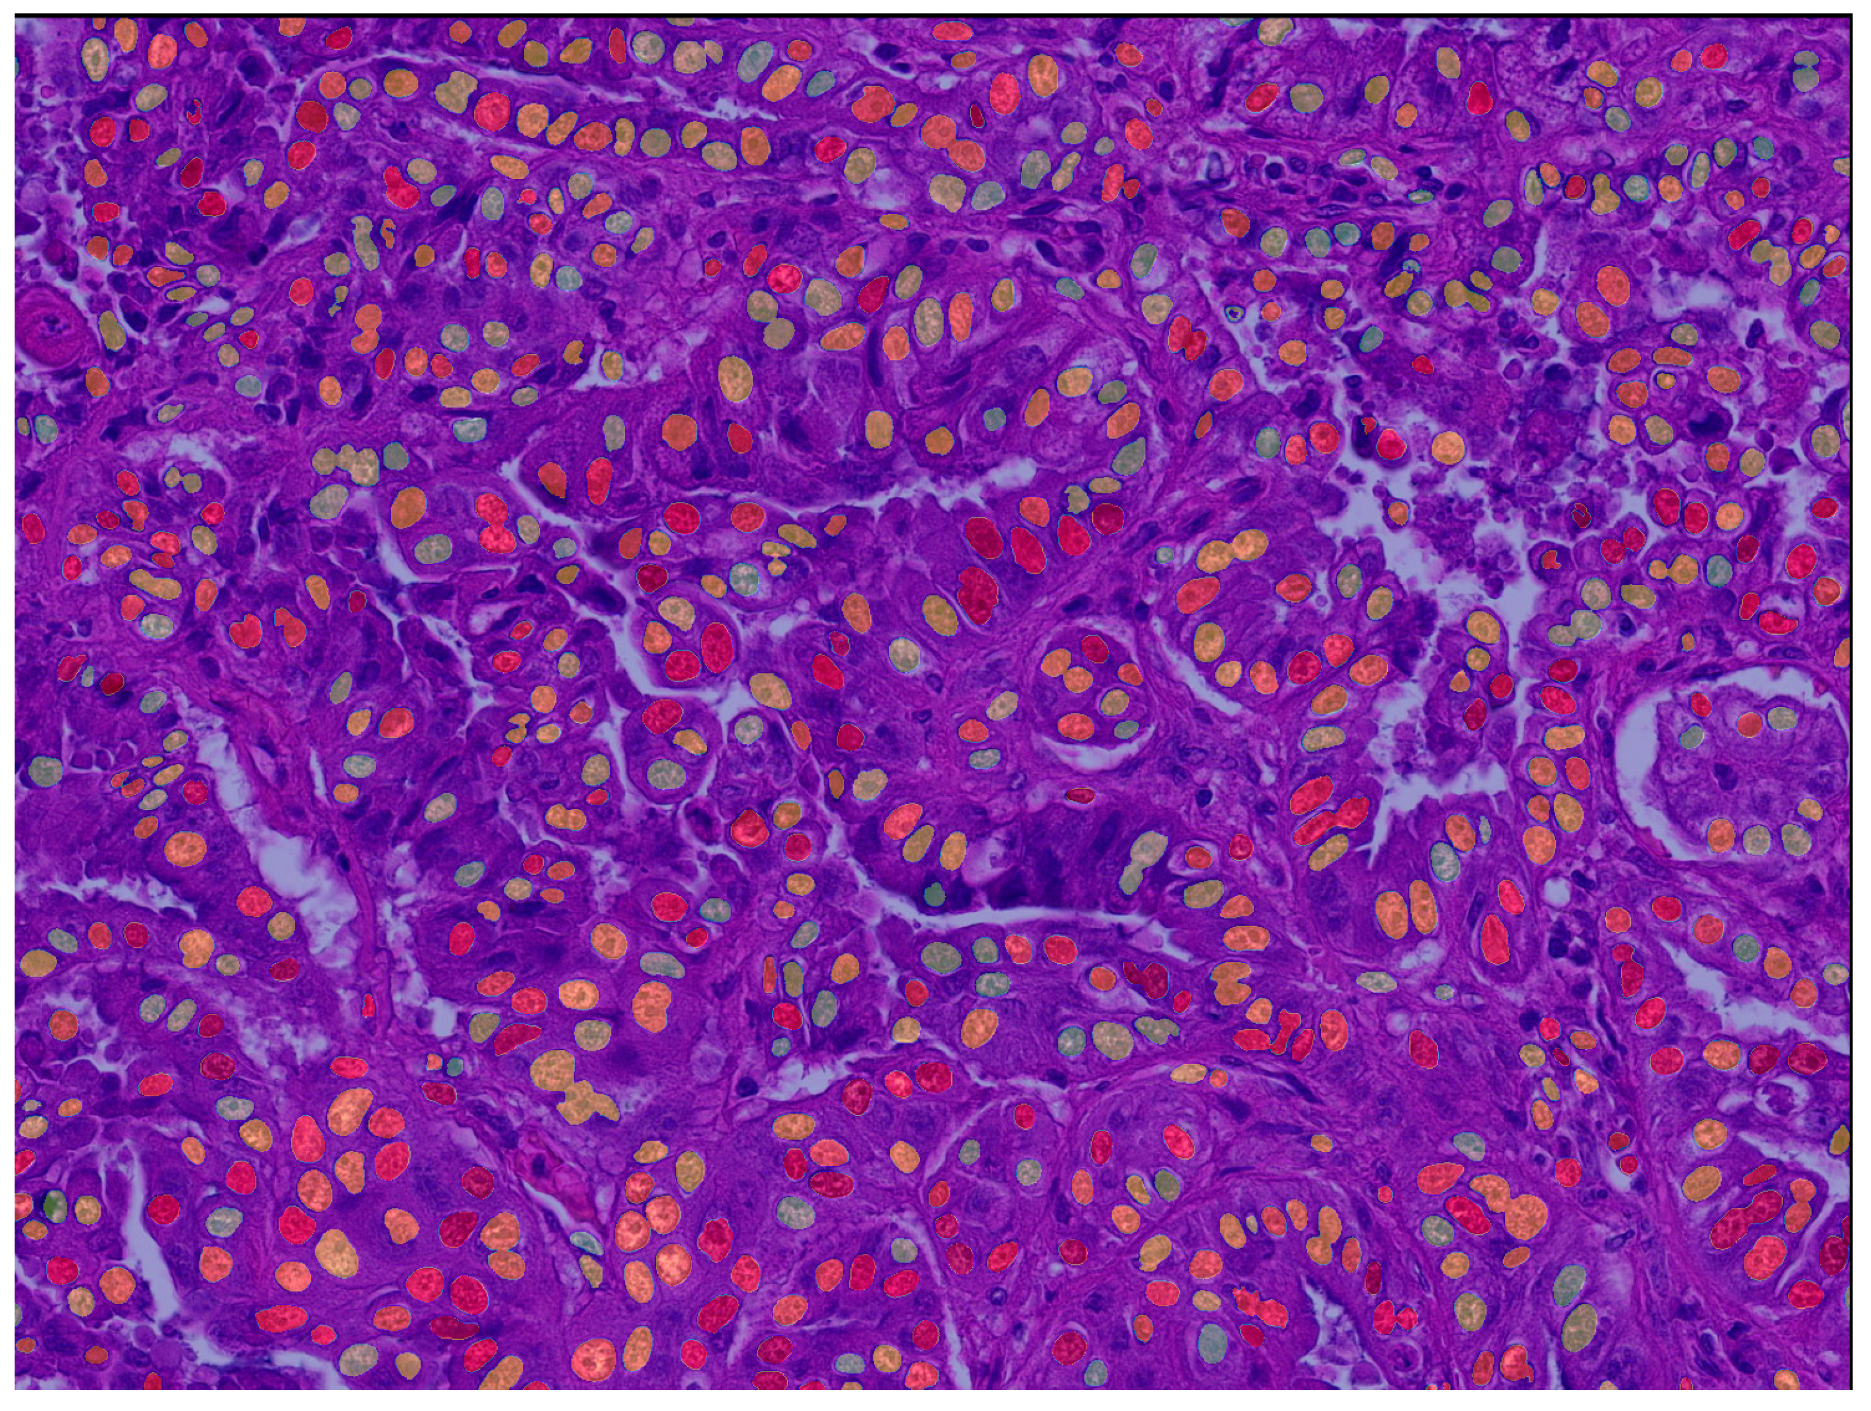

Deep Learning Segmentation Model

Algorithmic Morphometry

3.2. Test Accuracy of Algorithmic Morphometry

- The algorithm’s segmentation ability was good for nuclear size parameters and acceptable for shape parameters. Future studies may benefit from implementing filters and/or optimizing the algorithm to improve the model’s accuracy.

4.2. Test Accuracy of Algorithmic Morphometry